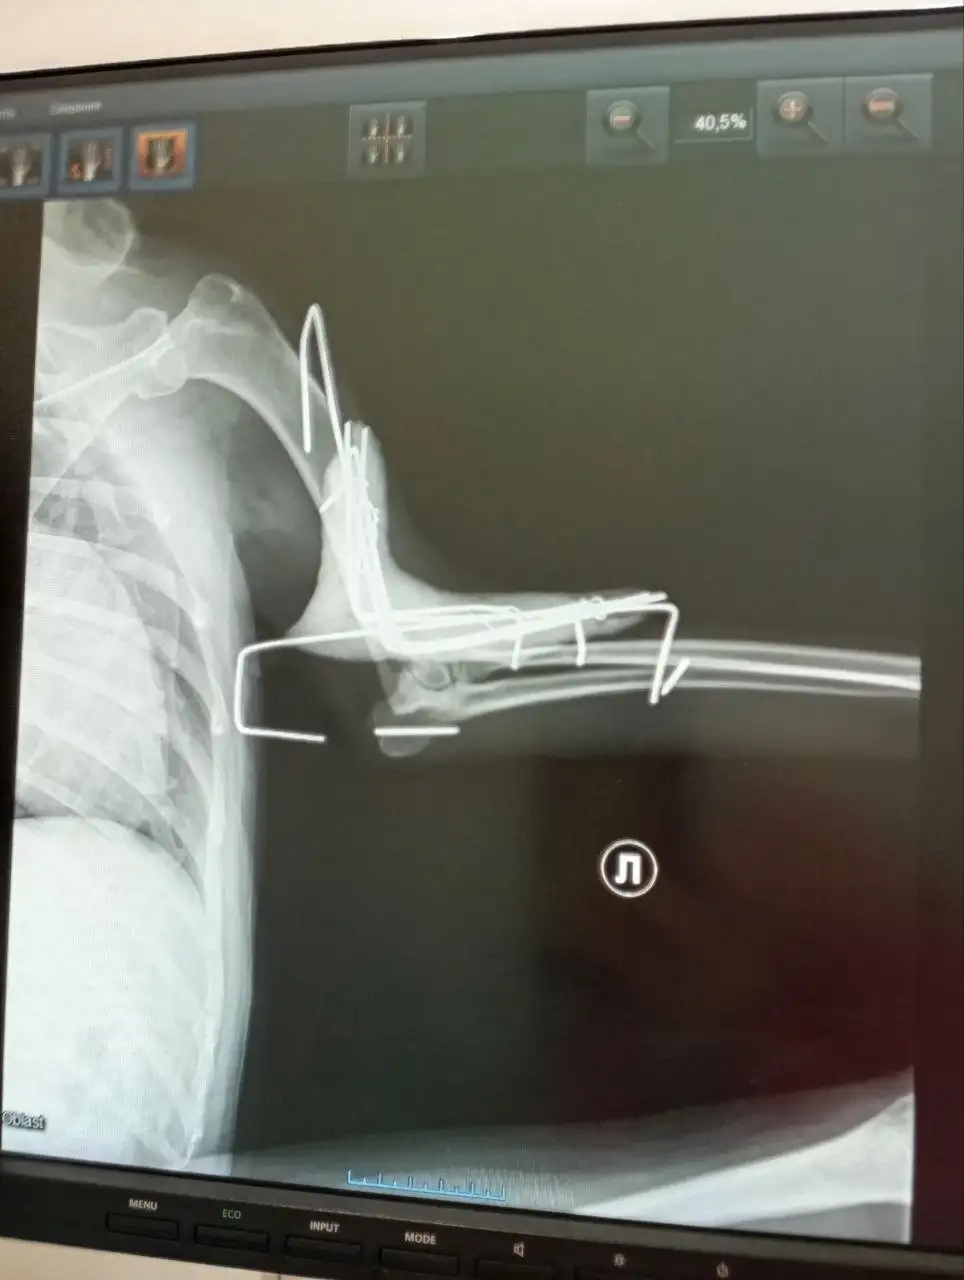

Сбор средств на лечение собаки по кличке Рыжуля. Сегодня ездили снимать аппарат Елизарова. Под анестезией (собака не ручная). Всё срослось удачно. Завтра платить за стационар и визит к врачу. Необходимо собрать определенную сумму. Спасибо всем, кто помогает. Без вас мы не справимся.